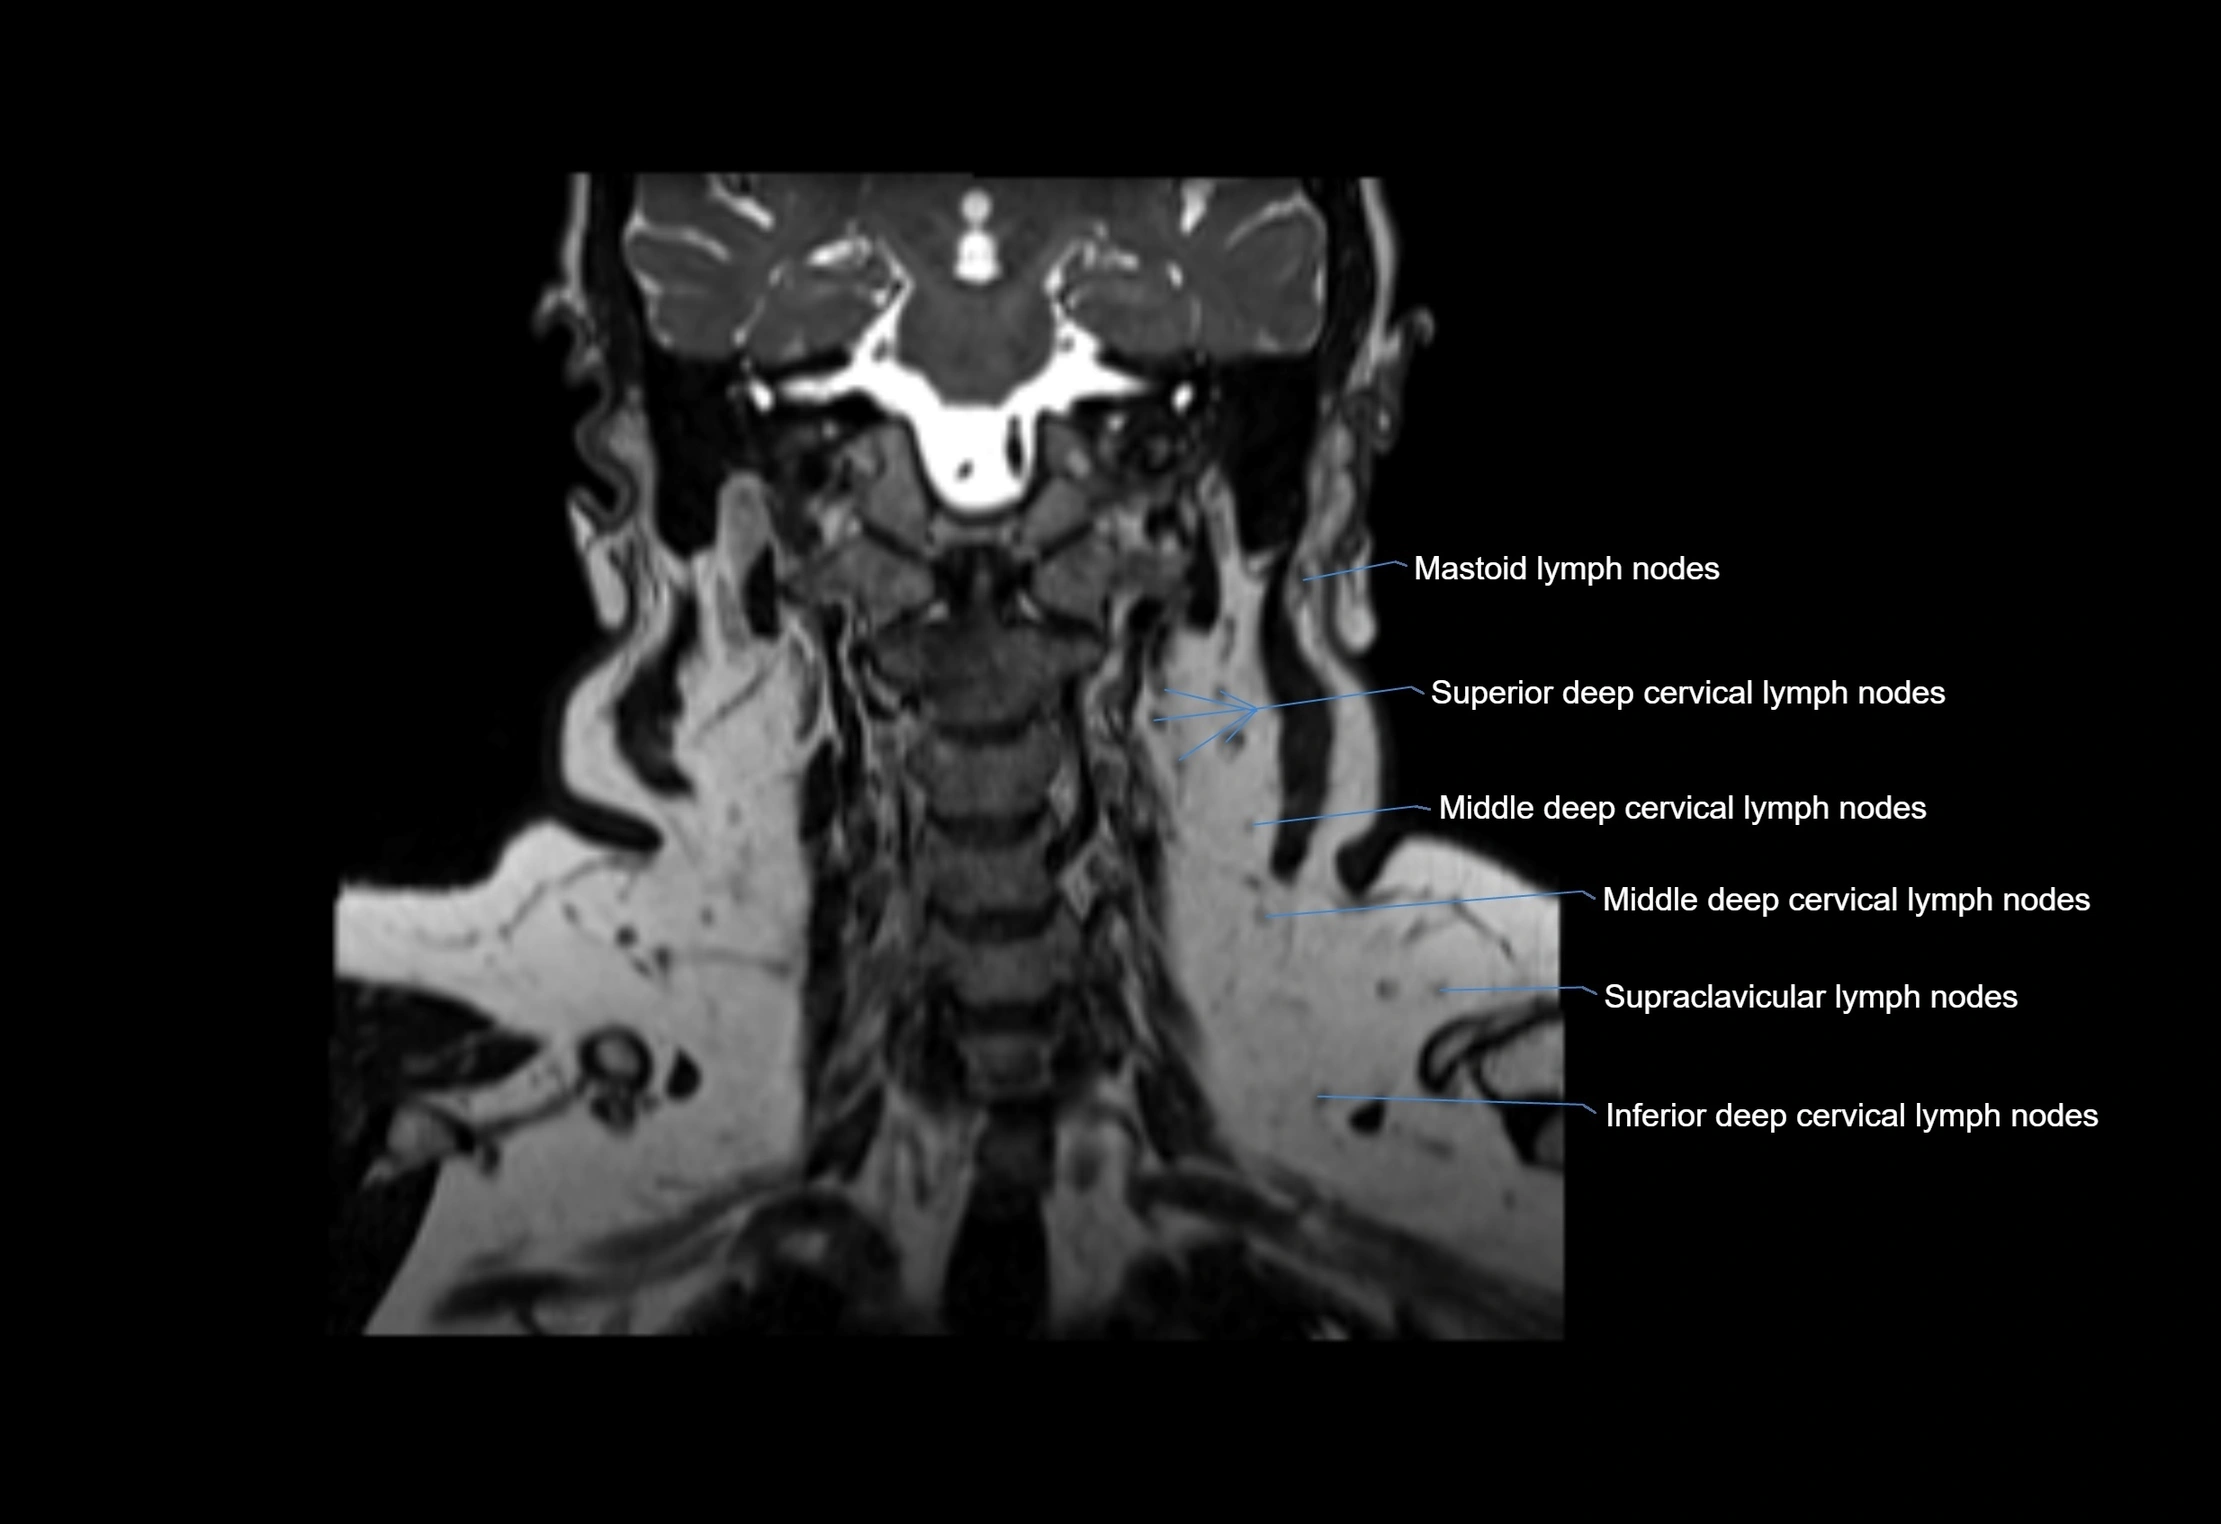

Location

• Found along primary lymph node chains, including preauricular, submandibular, parotid, and occipital regions

• Embedded in subcutaneous fat or superficial fascia, often lateral or posterior to primary nodes

• Variable in number; may occur unilaterally or bilaterally, depending on individual anatomy

MRI Appearance

T1-weighted images:

• Normal accessory nodes appear as small, oval hypointense to intermediate signal structures within subcutaneous fat

• Surrounded by hyperintense fat, enhancing contrast for visualization

• Pathological nodes may appear enlarged or rounded, sometimes with cortical thickening

T2-weighted images:

• Nodes show intermediate signal, with surrounding fat bright

• Useful for detecting edema, inflammation, or infiltration

• Fatty hilum may appear slightly hyperintense relative to cortex

MRI images

image